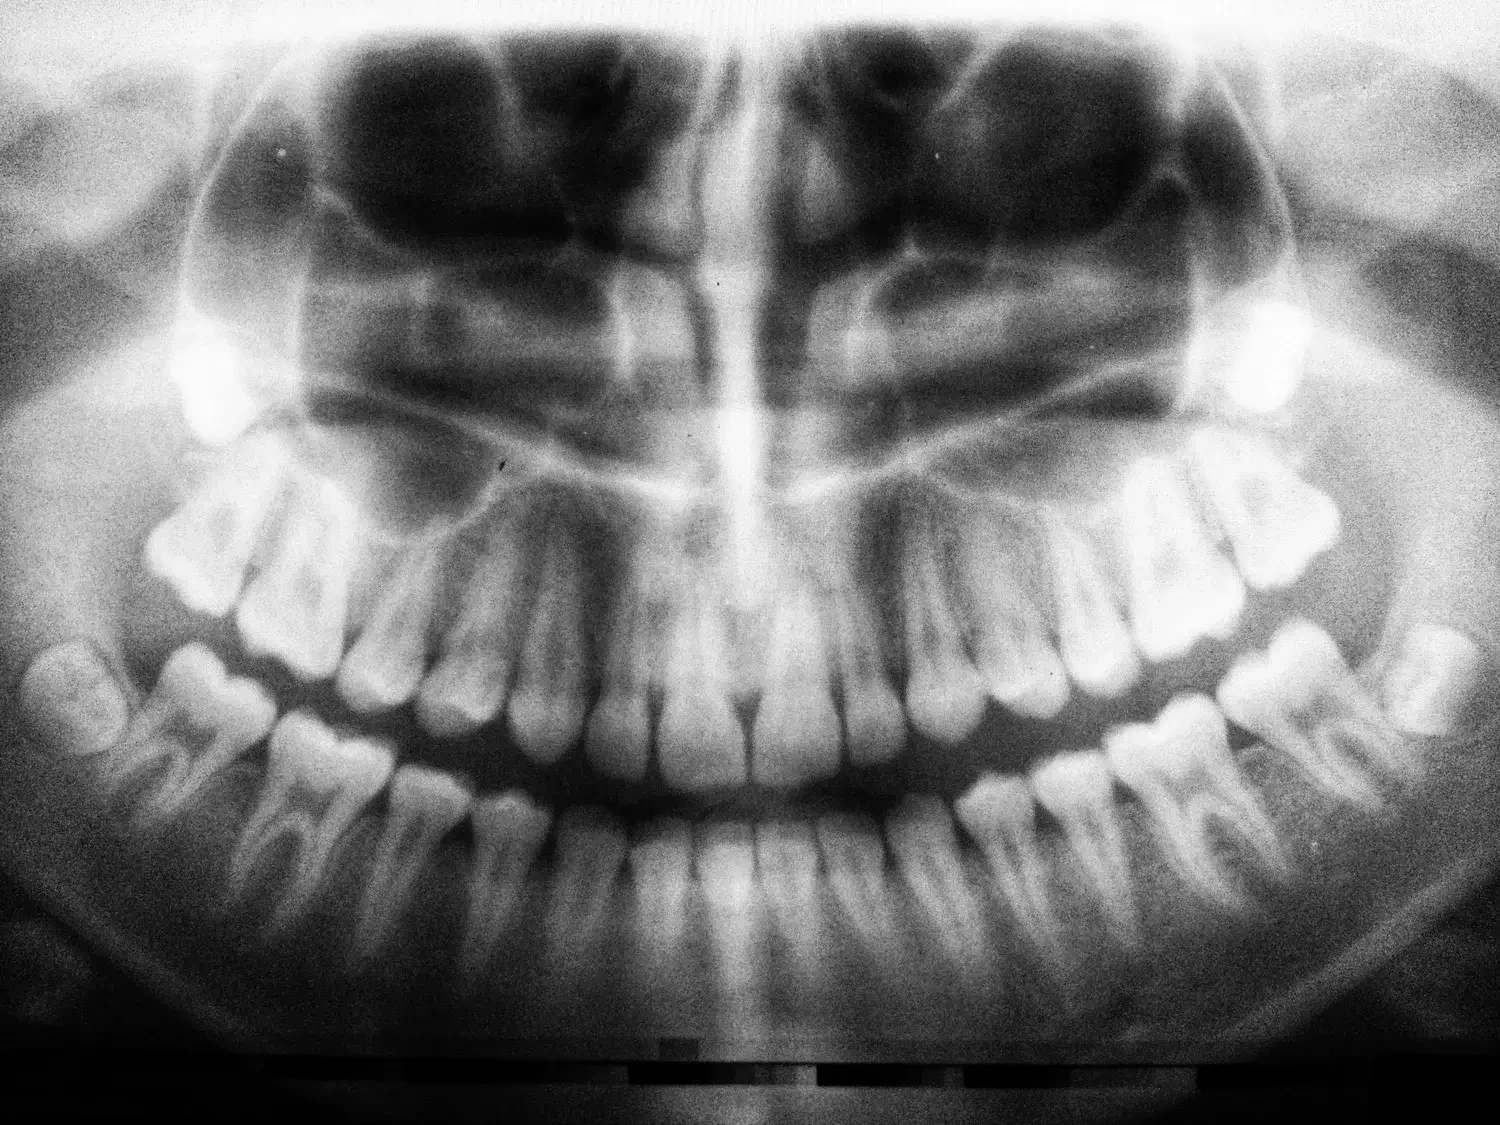

En Textbook Orthodontics, tratamos el prognatismo como un problema dental grave. Un prognatismo se produce cuando los dientes inferiores se extienden más allá de los dientes frontales superiores cuando la boca está cerrada. Esta desalineación puede provenir de problemas con la estructura de la mandíbula (prognatismo esquelético) o con los propios dientes (prognatismo dental).

Tipos y gravedad de los prognatismo

Los prognatismo se suelen clasificar en tres categorías principales -Clase I, II y III- en función de la alineación de los dientes y los maxilares:

Prognatismo Clase I: La forma más leve, en la que los dientes inferiores se superponen ligeramente a los superiores.

Prognatismo Clase II: Muestra una proyección más notable de los dientes inferiores más allá de los dientes superiores.

Prognatismo de Clase III: La forma más grave, caracterizada por un maxilar inferior significativamente adelantado.